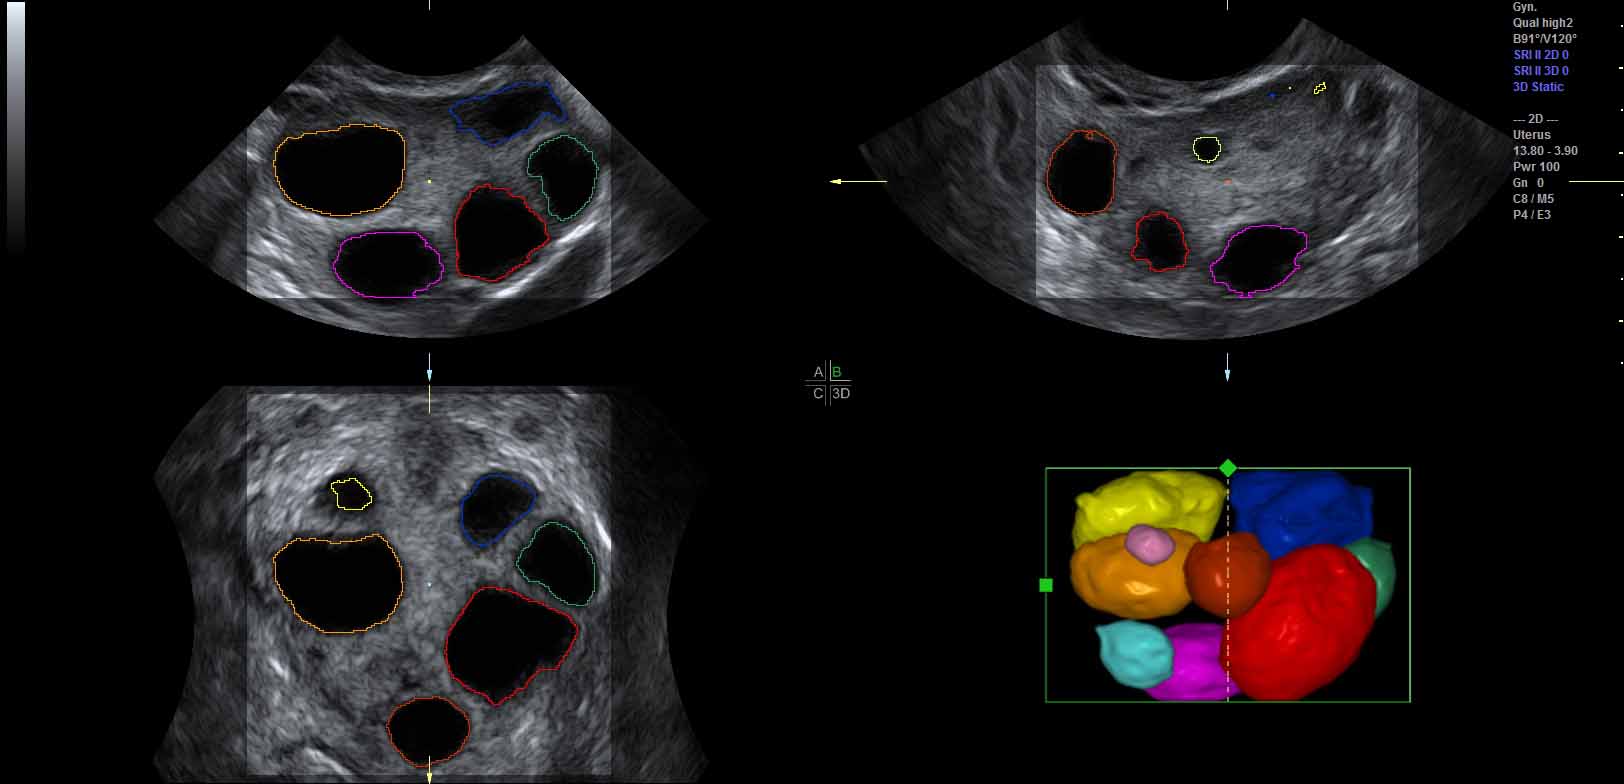

To increase robustness of the ultrasound segmentation, the various approaches are usually tailored for specific anatomies. Carneiro et al. have developed an automatic technique for segmenting the brain of a fetus carneiro08 . By first detecting the cerebellum, the system can narrow down the search for other features. On the other hand, segmentation is an extremely critical procedure which may obscure diagnostically relevant aspects of the anatomy under examination. Consequently, fully automatic segmentation techniques have not been implemented in clinical systems so far, with the exception of a method for follicle volumetry deutch09 , as shown in figure 3.

Feature extraction can be computationally costly. In-vivo 3D ultrasound examination cannot always afford the extra time necessary to extract the interesting structures. Therefore clipping is commonly used tool in live visualization of 3D ultrasound. Interactively removing regions which are not interesting, the user gets a clear view of the features normally occluded. Sakas et al. developed a clipping tool in their ultrasound visualization system sakas95 which is nowadays a standard feature in commercial 3D ultrasound systems. The user can in-vivo segment the dataset using three approaches. Drawing on one of the three axially-aligned slices, selecting everything along the current axis and within the sketch. Another tool is based on sketching directly on the 3D rendered scene. Each voxel is the projected onto the screen and removed if it lies within the marked area. The third clipping tool is based on the distance from a single mouse-click on the view-plane. A hemispherical wave front is propagated from the seed-point and stops when the voxels reach user-specified threshold. Figure 4 show an example of clipping implemented in the GE Voluson machines magicut99 .